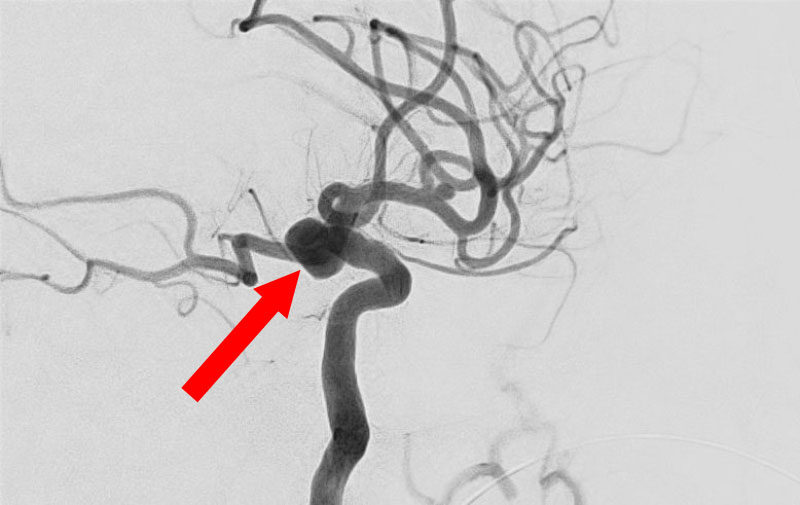

'25年10月

くも膜下出血

前交通動脈瘤破裂

60代

救急外来

No.1588 手術前

No.1588 手術中

No.1588 手術後